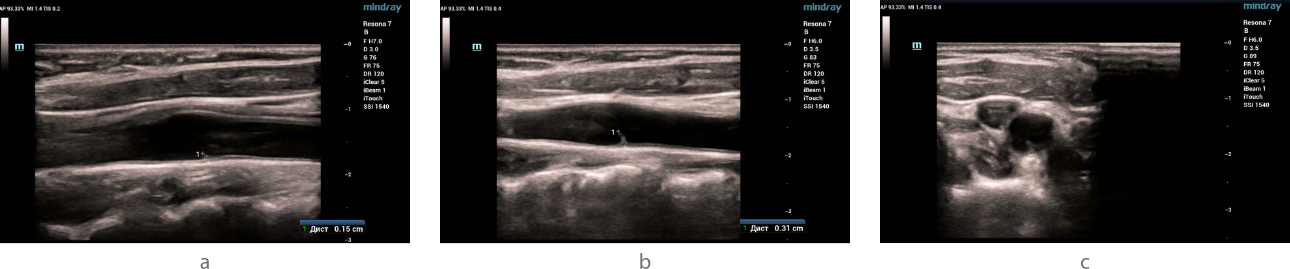

Ultrasound examination - B- mode

Ultrasound examination (ultrasound) of the carotid and vertebral arteries was performed on the Resona 7 ultrasound machine (Mindray, China) using the L9-3U linear probe. When examined in B-mode in the area of bifurcation of the common carotid artery, a hyperechoic linear structure (slightly expanding at the base) with clear even contours, without signs of flotation, having a slope towards the internal carotid artery and protruding into the lumen of the vessel was visualized on both sides along the posterior wall: on the right by 1.5 mm, on the left by 3.1 mm (fig. 1). No structural changes were detected in other carotid and vertebral arteries.

Fig 1. Ultrasound of the carotid sinus in B-mode.

In the bifurcation of the common carotid artery, markers indicate a linear hyperechoic signal with dimensions on the right (a) and left (b) in the longitudinal scanning plane. The type of hyperechoic signal (indicated by the arrow) in the left common carotid artery in the transverse scanning plane (c).